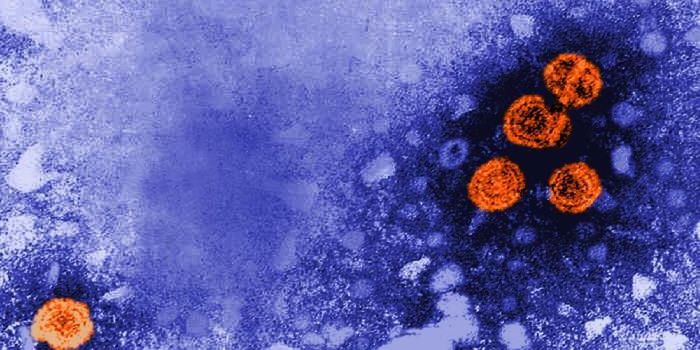

NOV 29, 2021MicrobiologyIt's estimated that about 240 million people worldwide have an HBV infection. Hepatitis B infections are linked to t ...